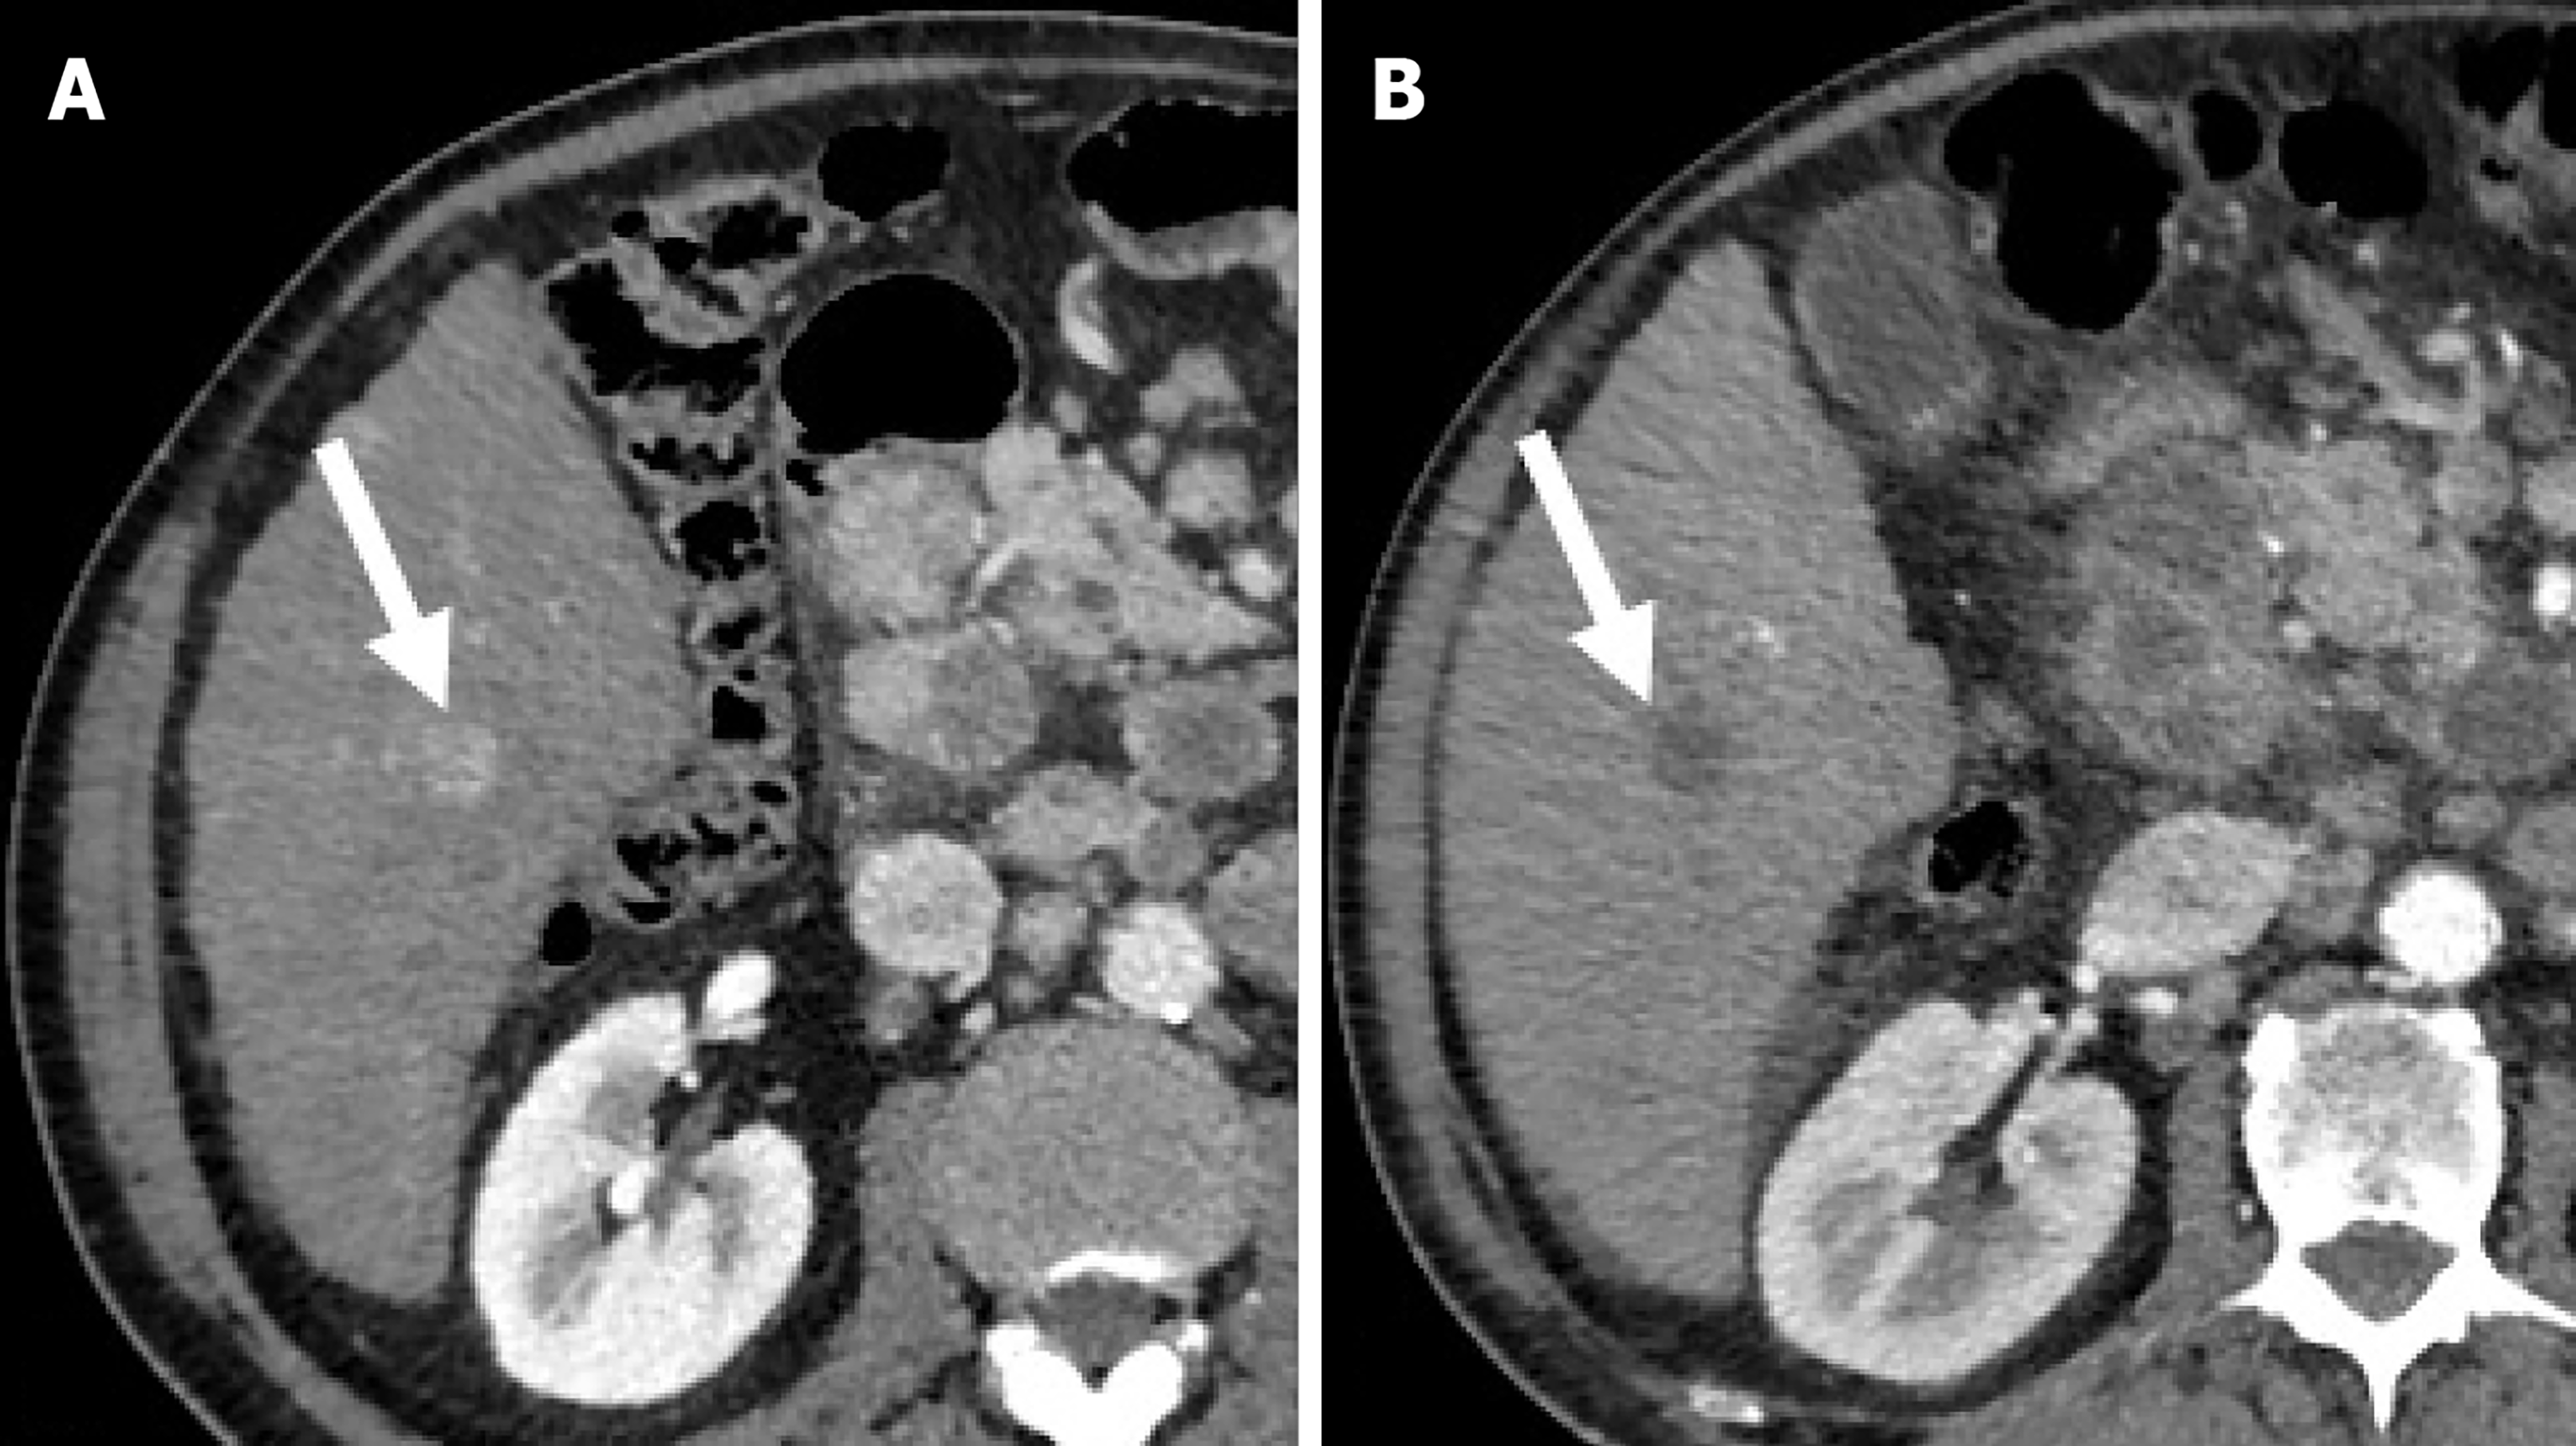

Figure 2 Residual hepatocellular carcinoma after trans-arterial chemoembolization in a 72-year-old man with hepatitis C virus-related hepatic cirrhosis.

A: On unenhanced computed tomography obtained one month after trans-arterial chemoembolization the residual tumor (dotted arrow) shows no Lipiodol retention and the necrotic tumor (arrow) shows homogeneous Lipiodol retention; B: On hepatic arterial phase the residual tumor shows enhancement and the necrotic tumor shows no enhancement; C: On delayed phase the residual tumor shows wash-out.